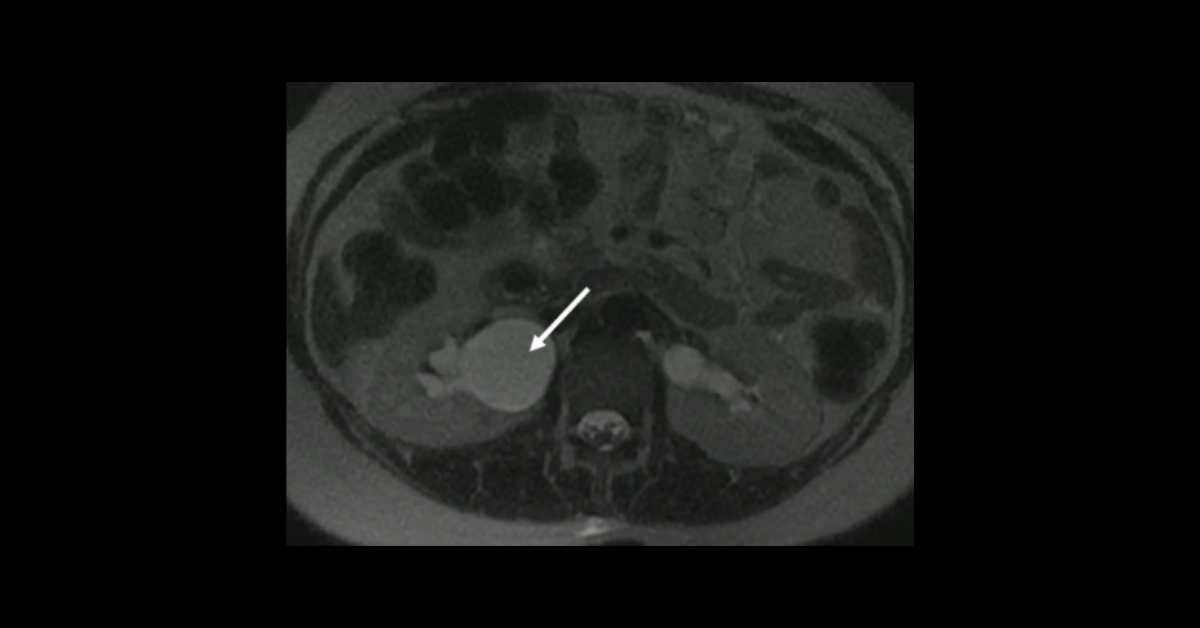

Presented by Ashish Khandelwal, MBBS, MD at Practical Radiology 2025. This talk will allow you to understand appropriate use of multimodal imaging in pregnant patient and know the imaging features of commonly encountered acute abdominopelvic conditions during pregnancy.